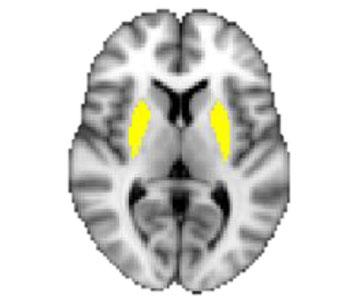

Poverty and Neuroscience

Jordan Anderson

Economics

Ethics

Medicine

Policy

Psychology

Sociology

Human Ecology

Physiology

Social Science

Spotlight